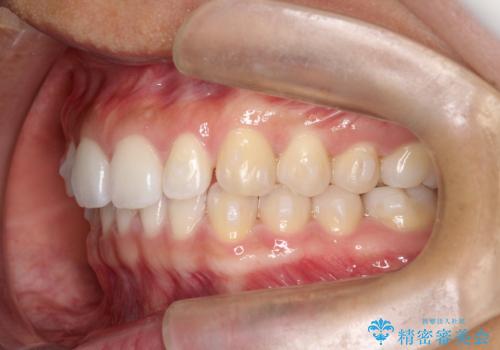

すきっ歯のインビザラインによる目立たない矯正

- すきっ歯を治したいとのことで来院されました。

上下ともに前歯に隙間がありました。

目立たない装置をご希望のためインビザラインで矯正治療を行うこととしました。

使用時間を守っていただけたので、スムーズに治療を終わることができました。